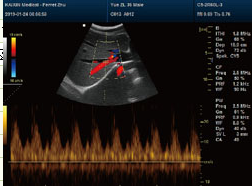

彩超穿刺是一种在超声实时引导下,用穿刺针精准进入体内病灶并取样或治疗的操作,主要用于组织活检、积液引流或药物注射。其核心步骤包括定位病灶、消毒麻醉、实时穿刺、取样处理,具有精准安全、创伤小的特点。 一、操作前准备 1、患者评估:医生会先通过超声确认病灶位置、大小及周围血管分布,评估穿刺可行性。患者需告知过敏史、用药情况(如抗凝血药需提前停药)。 2、签署知情同意书:医生会说明操作目的、风险及注意事项,患者需签字确认。 3、体位调整:根据病灶位置,患者需采取仰卧、侧卧等姿势,并保持稳定不动。 二、操作过程 1、定位与标记: 超声探头涂抹耦合剂后,在皮肤表面滑动扫描,找到最佳穿刺路径,避开重要血管和器官,用记号笔标记进针点。 2、消毒与麻醉: 对穿刺区域消毒并铺无菌巾,用细针在皮肤及皮下注射局部麻醉药,减轻疼痛。 3、实时引导穿刺: 医生持穿刺针沿预定角度缓慢进针,超声屏幕实时显示针尖位置。到达病灶后,通过负压吸引(如活检枪)抽取组织或液体。 4、样本处理: 取出样本放入保存液或玻片,送病理检查;若为引流,则连接引流袋排出积液。 三、术后处理 1、止血与包扎:穿刺点按压5-10分钟止血,覆盖无菌敷料,必要时用绷带加压。 2、观察与休息:患者需在留观区休息30-60分钟,监测有无出血、疼痛加剧或头晕等异常。 3、注意事项:24小时内避免剧烈运动,保持穿刺部位干燥;若出现肿胀、发热需及时就医。 四、技术优势与风险 优势:超声引导可实时观察穿刺路径,减少误伤风险;创口仅针眼大小,恢复快。 风险:少数可能出现局部出血、感染或气胸(如胸部穿刺),但发生率不足1%,及时处理即可控制。 五、适用场景 1、诊断用途:疑似肿瘤、甲状腺结节、乳腺肿块等需病理确诊。 2、治疗用途:肝脓肿引流、关节腔注射药物或卵巢囊肿抽吸。 彩超穿刺的准确性高度依赖医生经验及设备清晰度,建议选择正规医疗机构操作。